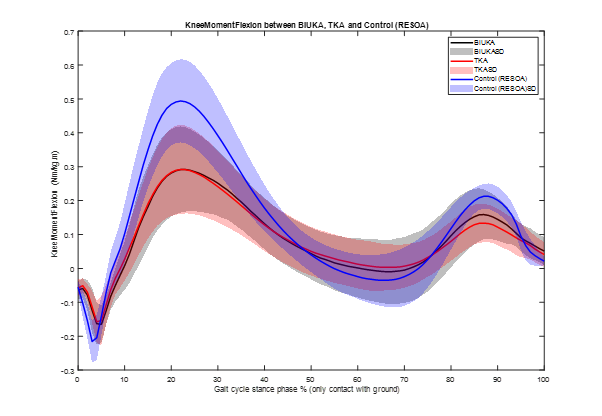

TRUCK RCT: Biomechanical function outcomes published in the Bone & Joint Journal online.boneandjoint.org.uk/doi/full/10.13… James Doonan Ortho-GRI Biomed Engineering